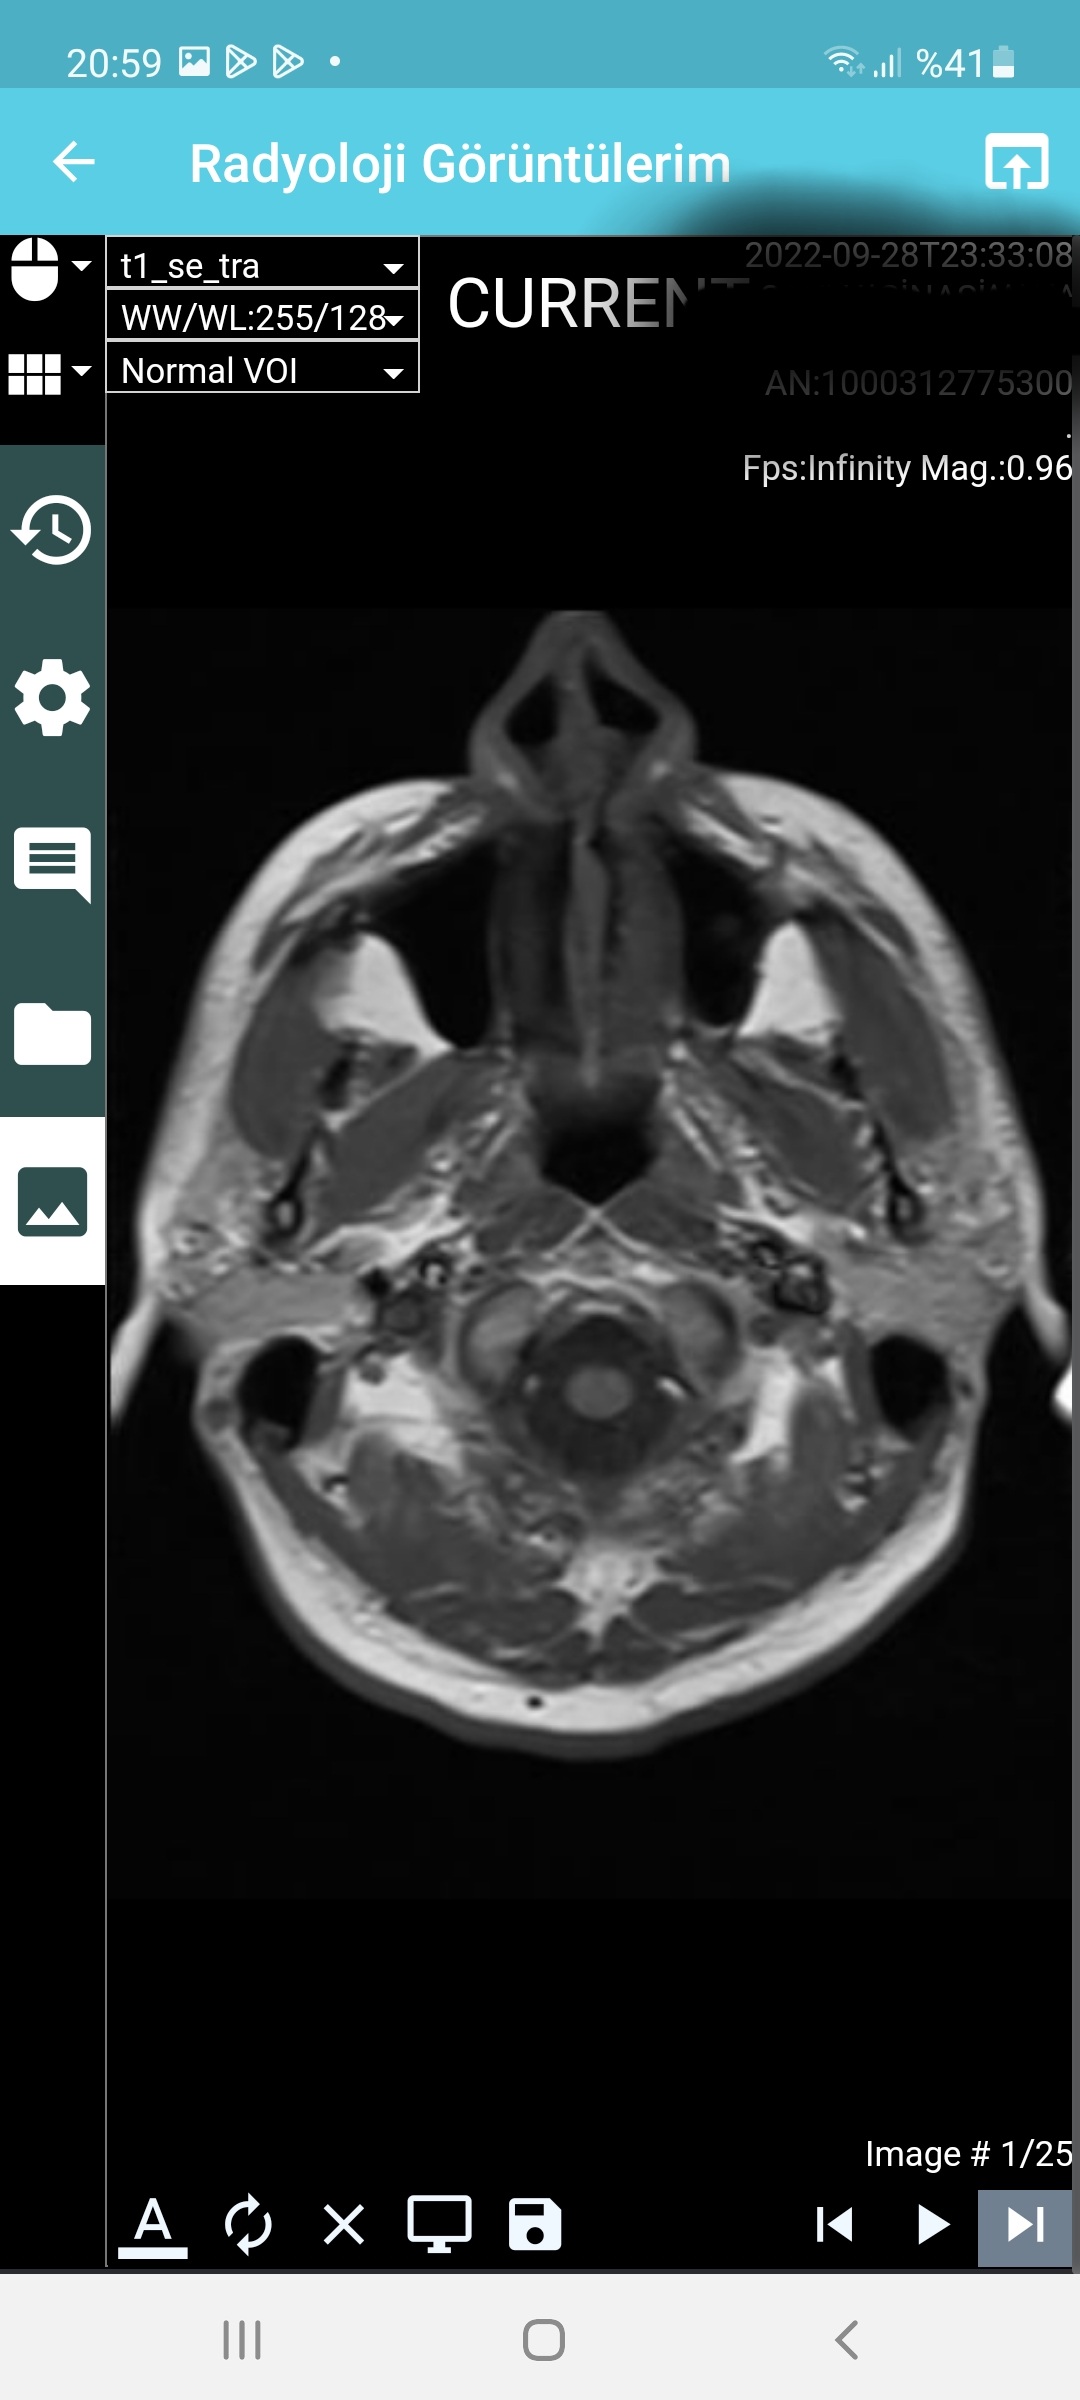

Arkadaşlar aranızda beyin emarı çektiren var mı yada bu konulardan anlayan ? Az önce emardan çıktım, emara sokan teknisyen pantolu ve kemerimi çıkartmadan emara soktu beni. Eee hani metal eşya ile girmek sakıncalı ve yasak degilmiydi? Şuan beynim şişmiş gibi acayip ağırlık var beynimde . Umarım bu emar sağlığa zararlı değildir. Radyasyon olmadığı için zararsız diyorlar ,umarım doğrudur. Hadi bunu geçtim ama o kemer umarım emar sonuçlarını etkilemez. < Bu mesaj bu kişi tarafından değiştirildi berlin007 -- 28 Eylül 2022; 23:49:8 > < Bu ileti mobil sürüm kullanılarak atıldı > |